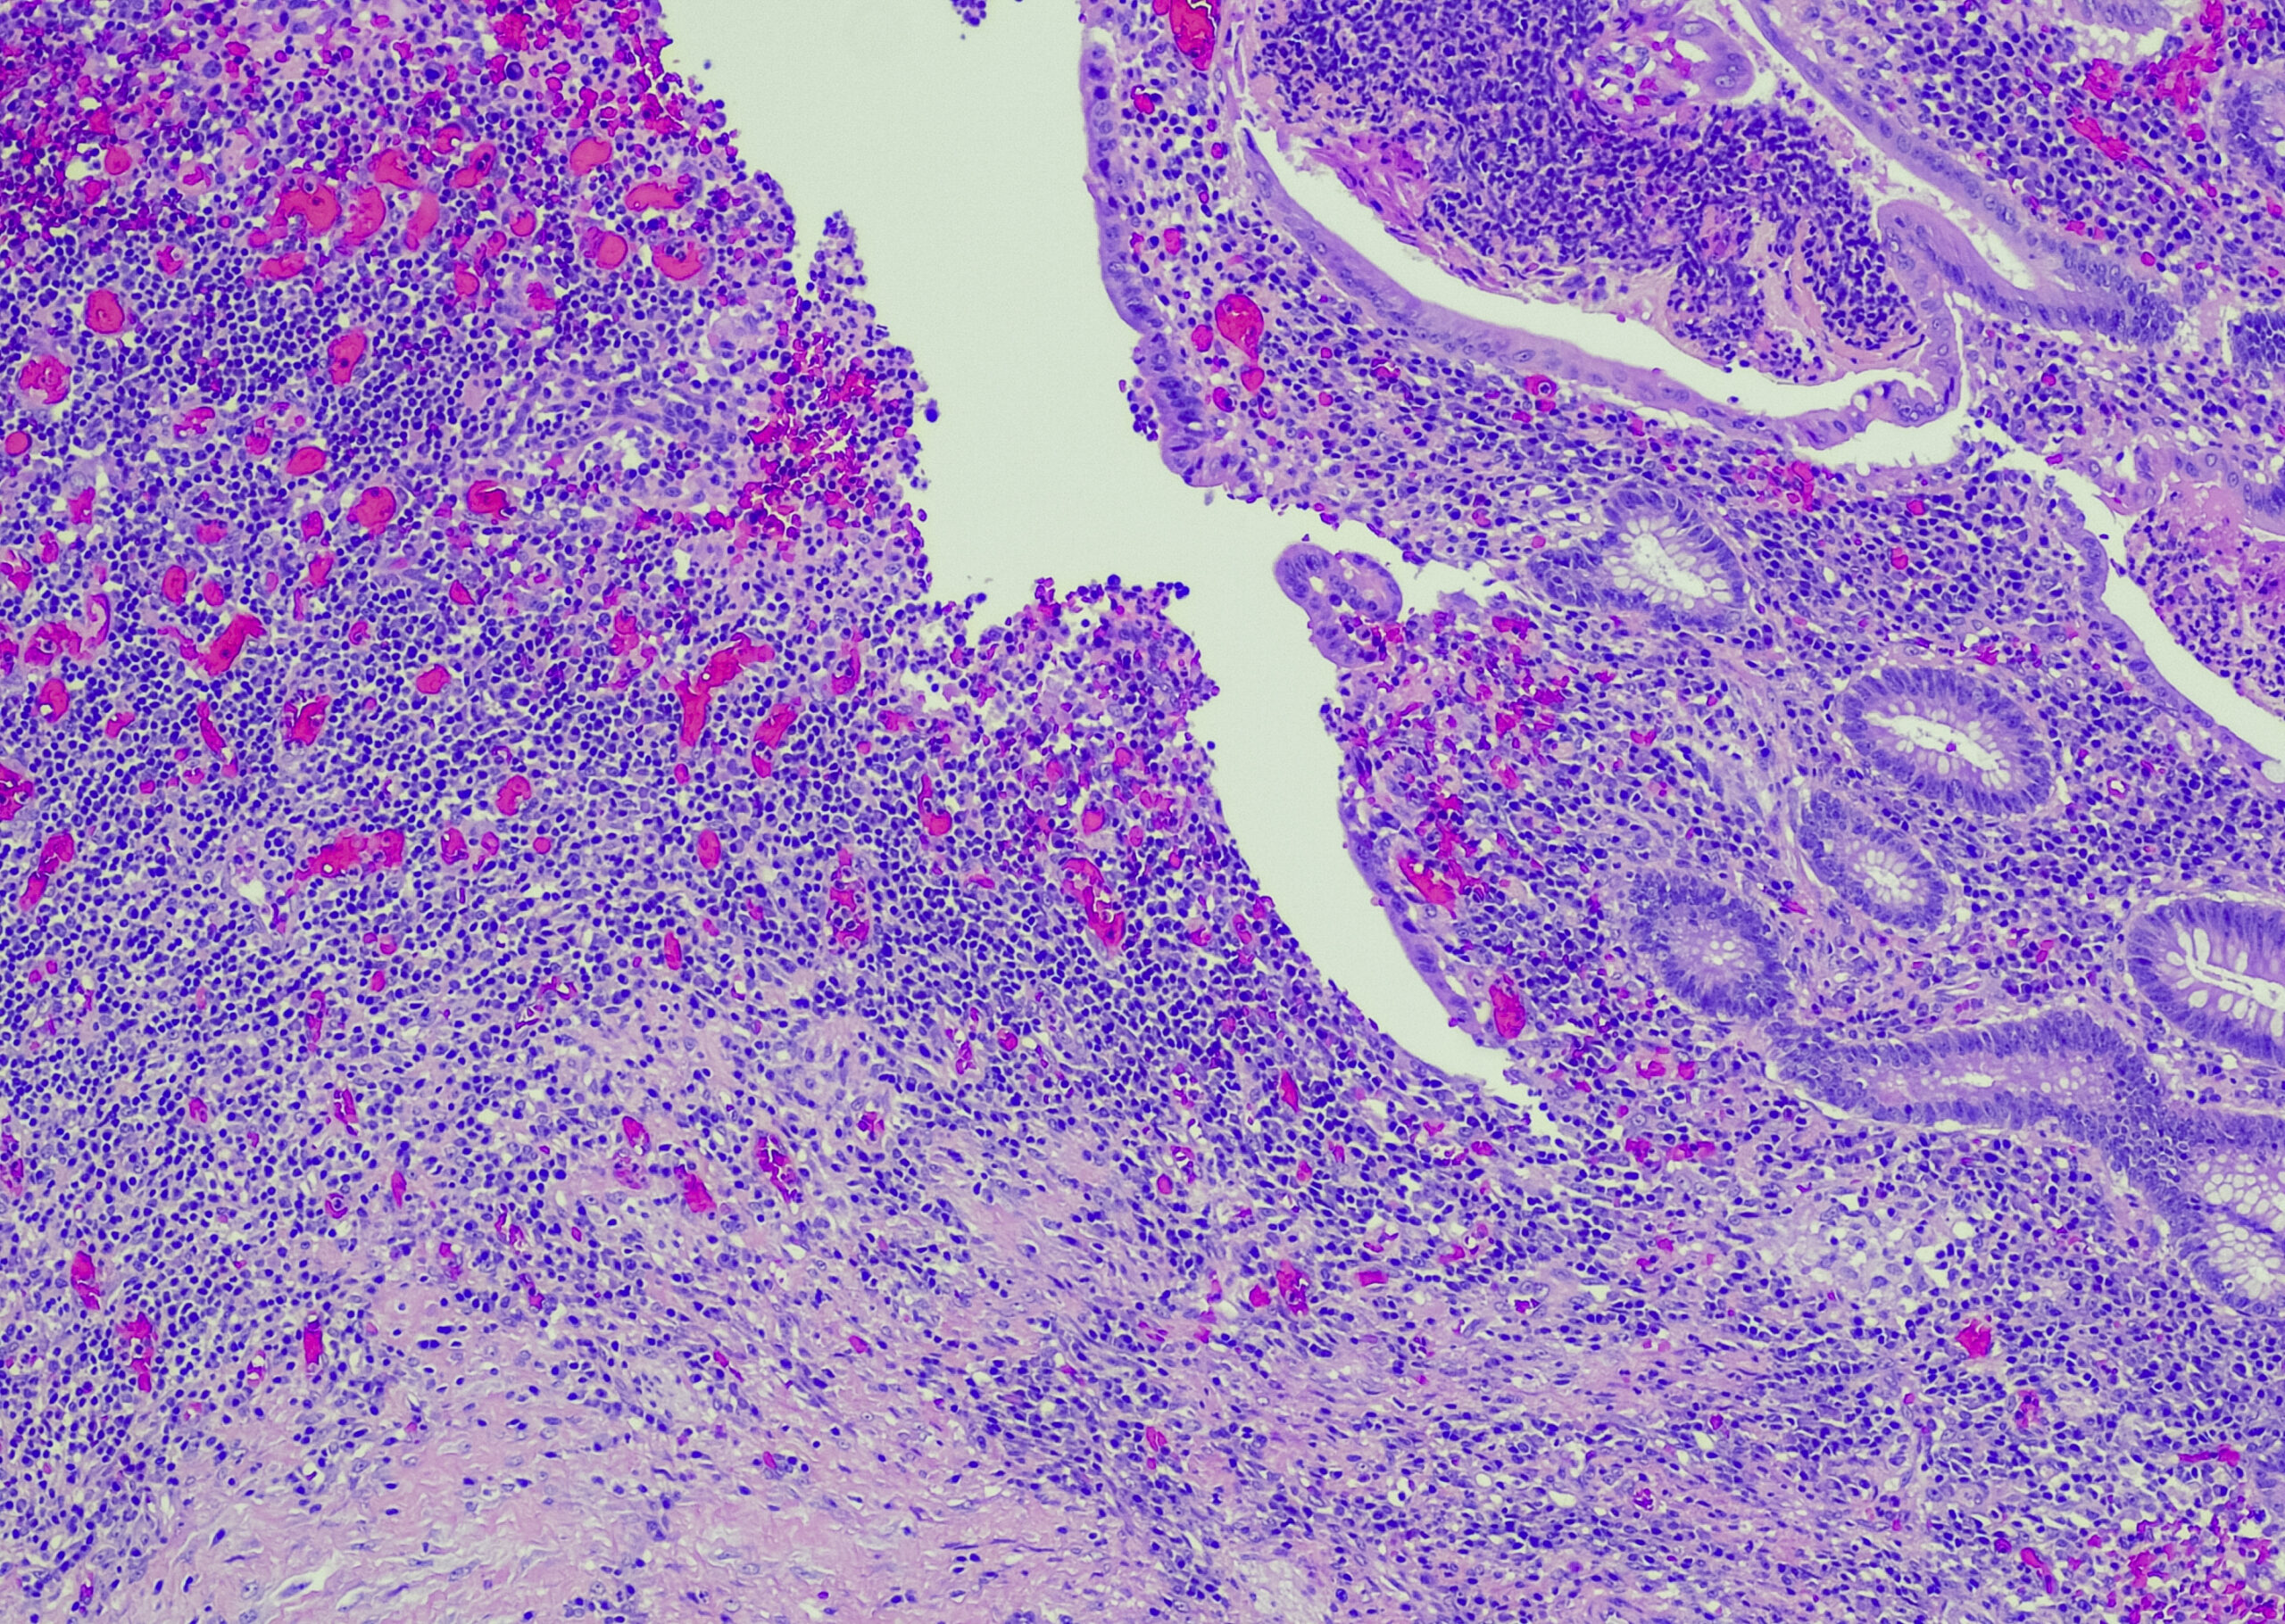

Multilocular cystic renal cell carcinoma (MCRCC)